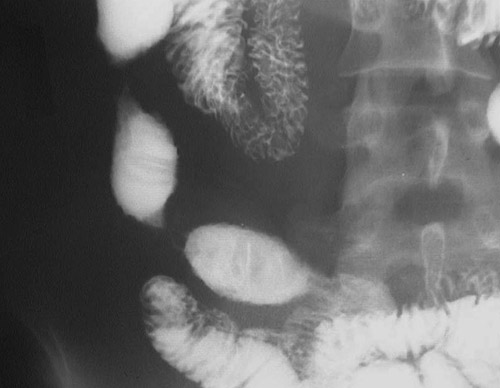

This upper GI series reveals a proximal and a distal segmental area of stricture in the terminal ileum, consistent with Crohn's disease.